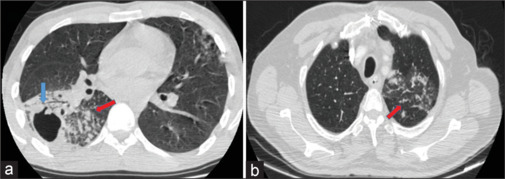

Objectives: Tuberculosis (TB) poses a serious health risk in Turkey and globally and is often difficult to diagnose. It may be sometimes necessary to obtain bronchoalveolar lavage (BAL) and, in some cases, biopsy samples via bronchoscopy to acquire an adequate sample. Our aim is to assess the contribution of transbronchial lung biopsy (TBLB) alongside BAL in diagnosing TB. In addition, we will evaluate the risk of pneumothorax associated with TBLB and determine the overall risk-benefit ratio.

Methods: Flexible fiberoptic bronchoscopy (FFB) reports performed for suspected TB between March 2011 and July 2018 were retrospectively reviewed. Patients who had both BAL and tissue samples taken via TBLB were included in the study. Of the 606 patients included, age, sex, the lung area where the biopsy was taken, BAL and biopsy AFB and culture results, and complications such as pneumothorax and chest tube application were recorded.

Results: A total of 606 patients were included in the study. Of these, 391 patients were male (64.5%) and 215 were female (35.5%). A total of 37 (6.1%) patients had a positive culture for TB. Nineteen (59.4%) patients were positive on both BAL and tissue culture, while 5 patients were only positive on tissue culture. Pneumothorax developed in 34 patients (5.6%), 28 of whom required a chest tube.

Conclusion: Using various modalities such as BAL and TBLB together for diagnosing pulmonary TB can be advantageous when appropriate, particularly given the absence of significant complications during the procedure. Our findings indicate that incorporating TBLB alongside BAL impacted the diagnosis of pulmonary TB.